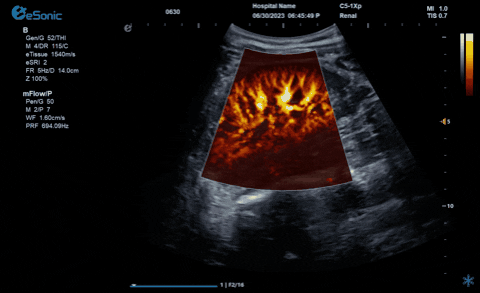

析“微”查异,识“微”见远

发布时间:2025-01-07

新航娱乐医疗的eHertz系列彩色多谱超声诊断系统凭借强大的RawVision?原数精准平台和SDBeam?软波声束合成技术推出专属的mFlow ?超微血流显像技术,该项技术可专用于极低速血流成像。彩色多普勒血流(CDFI)检查时,通常会将滤波器的频率设置为大约50hz,并随时调整标尺和增益,以便在背景噪声发生前显示小血管......